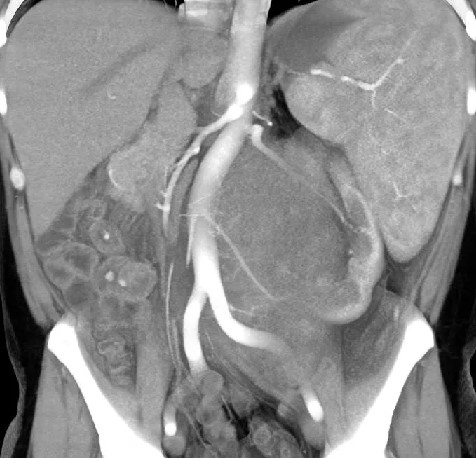

Магнитно-резонансная томография органов брюшной полости, забрюшинного пространства и позвоночника

МРТ органов брюшной полости и забрюшинного пространства ‒ это безопасный и высокоинформативный метод исследования, который позволяет не только уточнить локализацию опухоли, точные размеры новообразования и соотношение его с окружающими тканями, но и выявить метастатические очаги в печени и брюшной полости. Также МРТ дает возможность оценить состояние костных структур и мягких тканей позвоночного столба и позвоночного канала (рис. 6).

Рис. 6. МРТ нейрогенного образования забрюшинного пространства слева